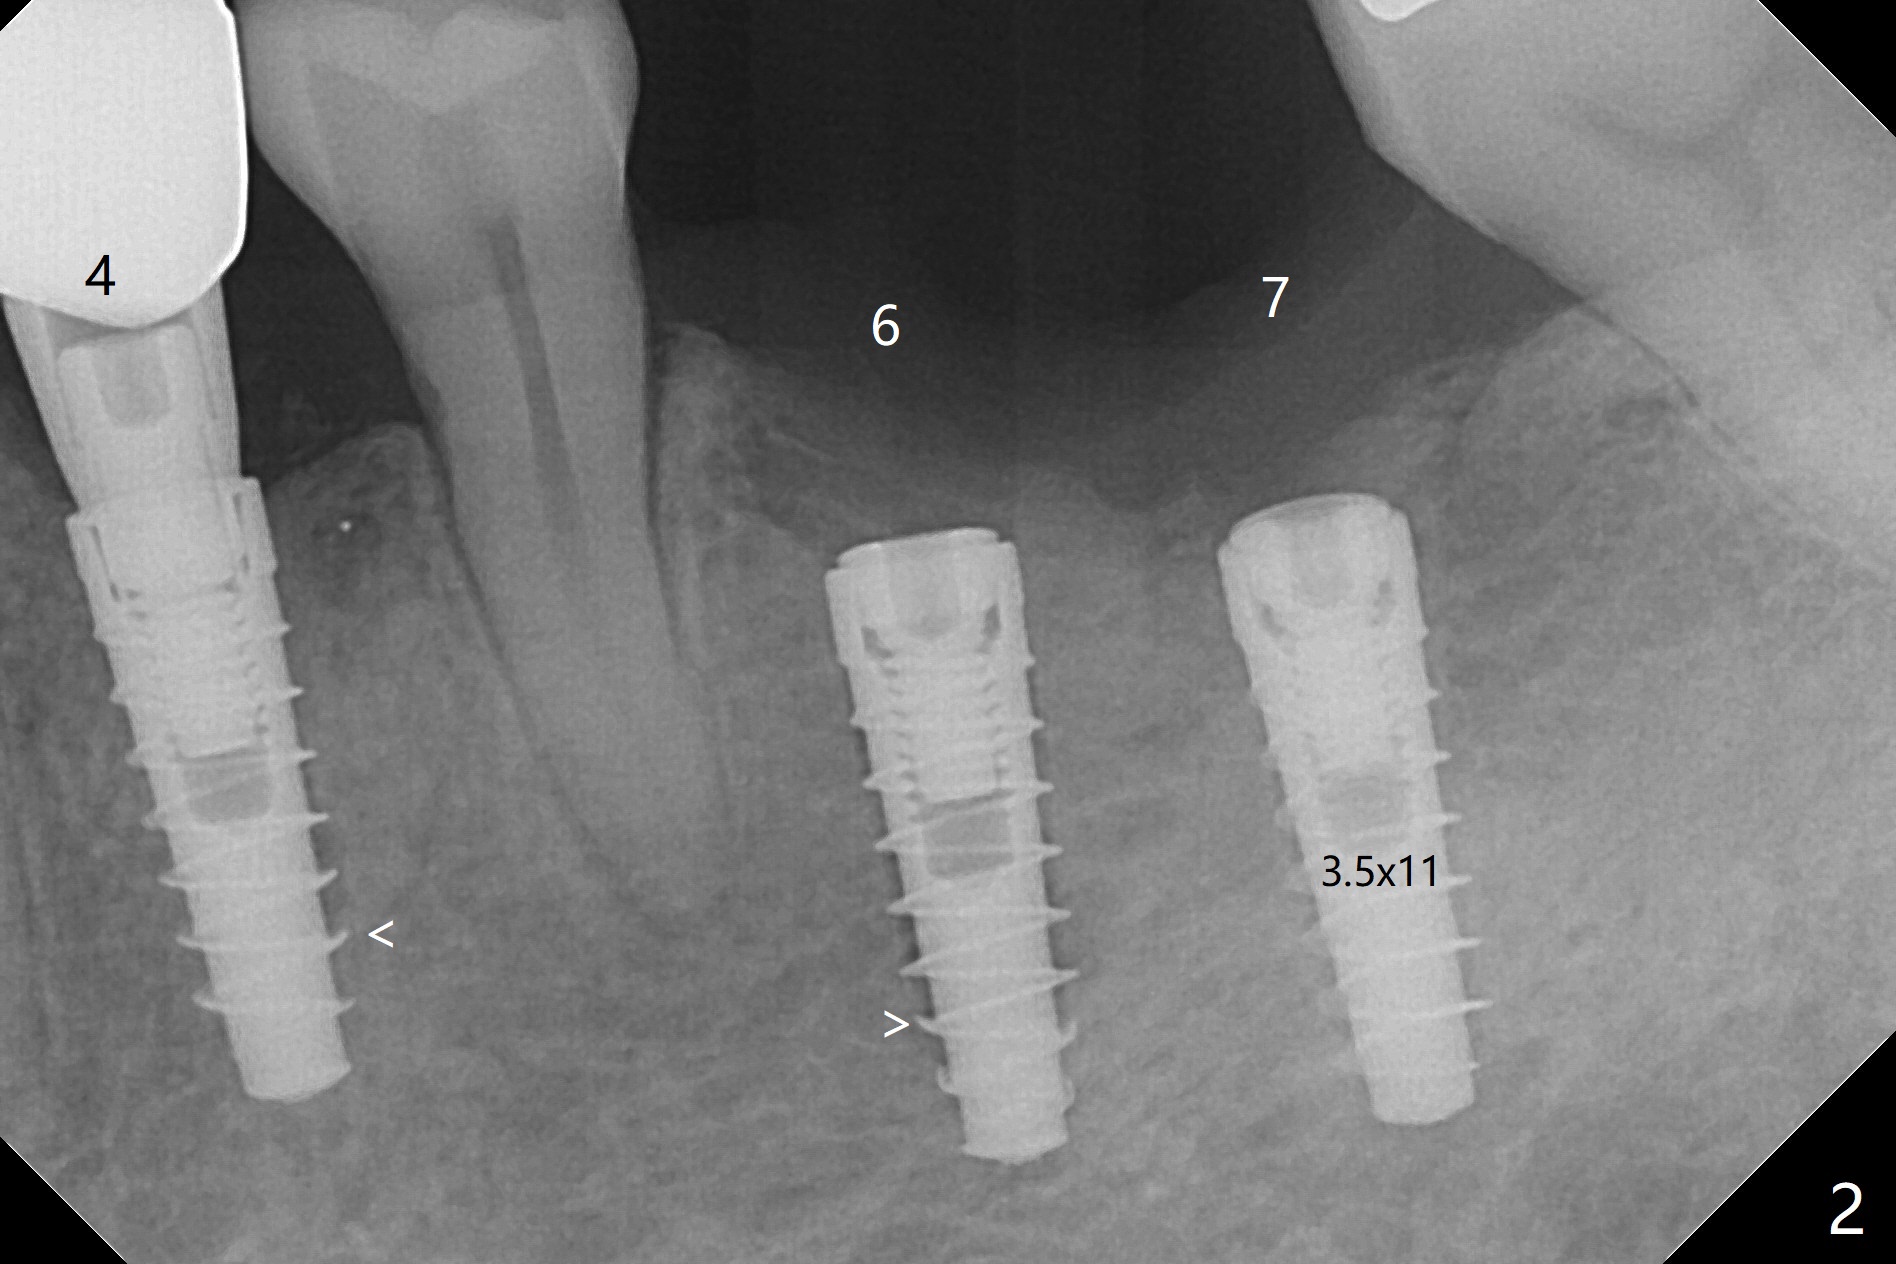

左下6,7导板设计种植两个小植体,牙槽嵴角化龈狭窄(图一:*),切开,钻洞,6处骨质密度高,钻头与植体直径必须一样,但是为了保证稳定性,最后1.5毫米钻头小0.5毫米,植体最后1-2毫米必须倒旋一次才能控制扭力不超过40Ncm,术后即刻根尖片显示4,6根尖部(密度2200单位,图二)螺纹弯曲(<),而7(密度670单位)钻头比植体小0.5毫米,植入扭力也大约40Ncm,不过螺纹没有变形。祸不单行,6植体冠部舌侧螺纹暴露约1毫米,放入自体骨后,盖膜(6个月),4-0铬羊肠线减张缝合(图三),牙槽嵴好像增宽了。术后两周伤口愈合(图四)。术后4.5个月切开暴露,尽管需要外科钻头去除植体冠部骨质,6舌侧植体螺纹仍暴露,放置4.5x3毫米愈合基台,7放置4x4(3)毫米修复基台(图五),但是接近8牙冠,无法修复,必须做局部牙齿矫正。术后7个月7放置3.4x3毫米愈合帽,6放置4.5x5.7(4)毫米修复基台,手拧紧,做临时牙冠,垫高,开始矫正;一个月后基台松动,扳手拧紧(30Ncm);7处3.4x3毫米愈合帽没有就位,由于远中牙槽嵴阻挡(图六:<)。